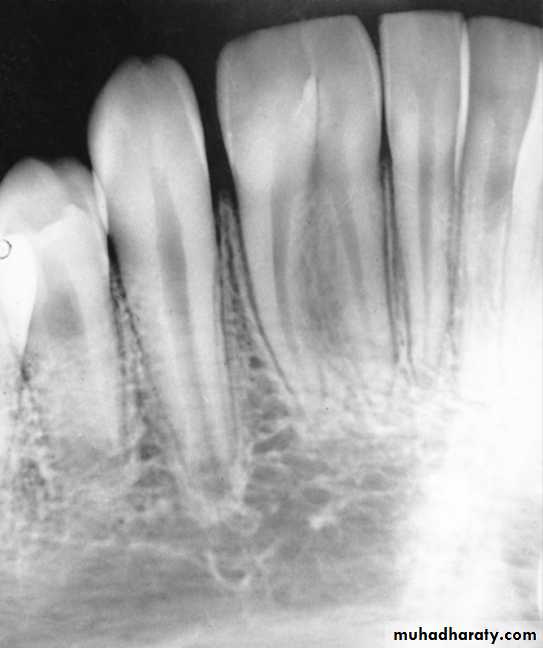

4. Dentinogenesis imperfecta.

Dentinogenesis imperfecta

Disturbances of the differentiation of the formative cells which are odontoblast

during histodifferentiation stage

Dentinogenesis imperfect

Abnormal root